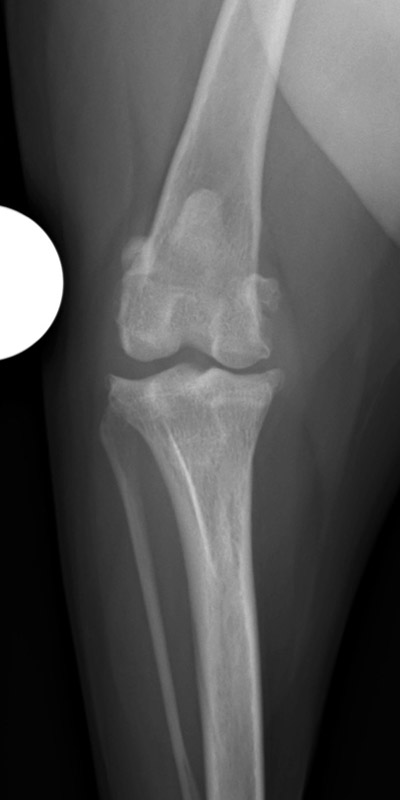

肘関節内骨折

アメリカン・コッカー・スパニエル(5歳)

車の窓から落下

手術前

手術後